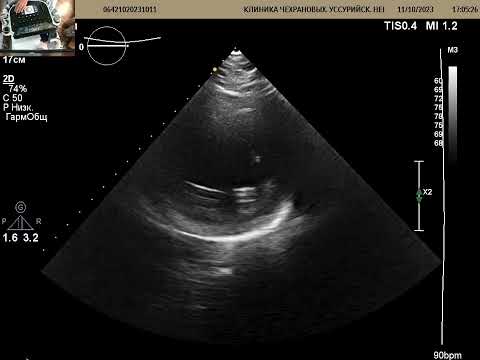

УЗИ сердца через 3 месяца после обширного инфаркта. ФВ 25%